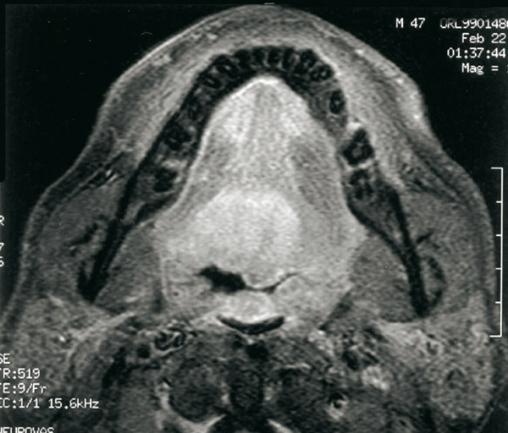

Tumeur de la base de la langue

IRM de base de langue : tumeur infiltrante.